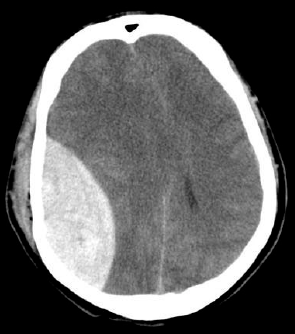

22

Q

¿Qué hematoma es este?

A

Epidural

21

¿Cómo se ve el hematoma epidural en TC?

• Biconvexo o lenticular

• Fx

• Importante Efecto de masa y herniación